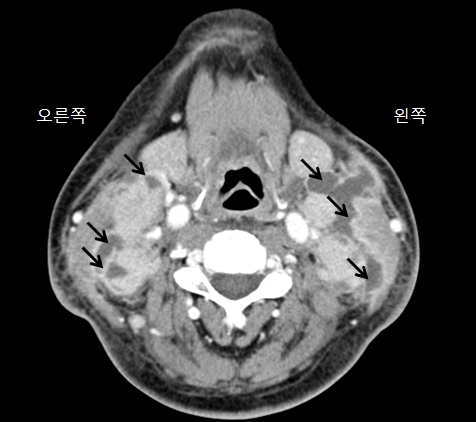

결핵성 임파선염(Tuberculous lymphadenitis)

결핵

결핵성 골수염

위장관 결핵

결핵성 복막염

속립성 결핵

폐결핵

결핵성 수막염